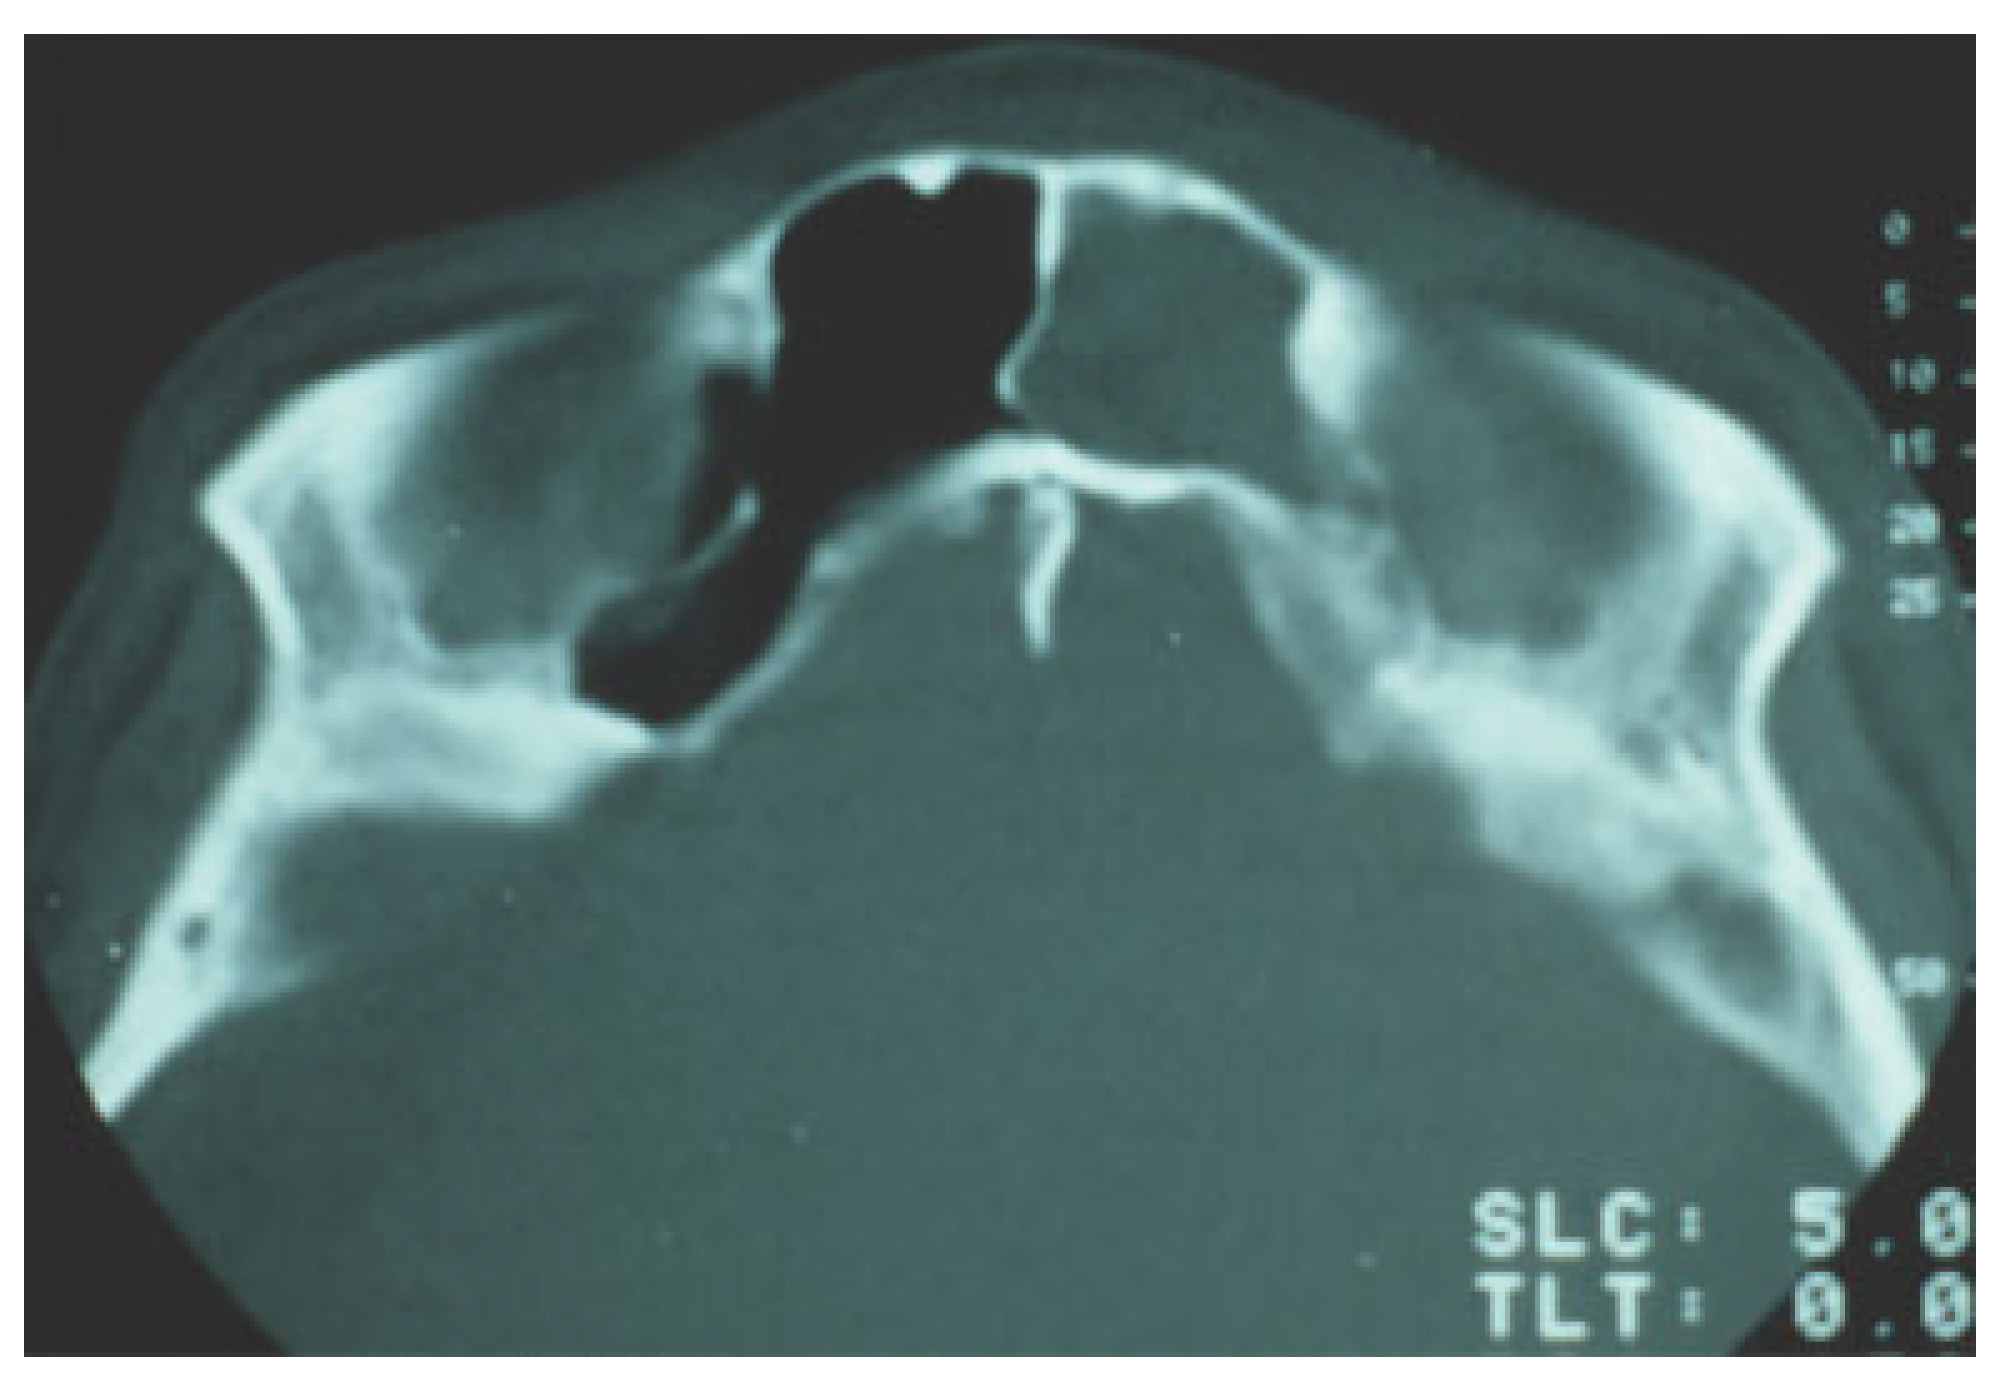

The advances in computed tomography (CT) technology have greatly enhanced diagnosis and treatment planning of frontal sinus fractures. CT scans have improved assessment of posterior wall and nasofrontal outflow tract injury. Nasofrontal outflow tract injury is found in 13 to 55% of the frontal sinus fracture cases[7]; thus, preoperative determination of patency, if possible, is crucial to management. The two imaging findings of outflow tractobstruction are a sinus air–fluid level and fracture involvement of the tract in the sagittal view.[8,9] The index of suspicion should be high of an injury to the drainage tract in the presence of associated nasoethmoid fractures (Figure 2).

Figure 2. Axial computed tomographic image of a patient with disrupted nasofrontal duct.